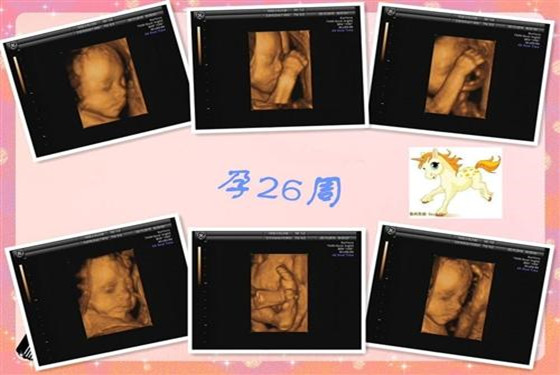

好比四维彩超,它是孕期怀孕的准妈妈必须做的检查项目,医生通过四维彩超可以查看胎儿的发育情况,方便医生诊断,也可以及早的发现胎儿畸形的问题。

四维彩超,它是整个孕期比较重要的检查项目,四维彩超检查范围比较广泛,它能很好的掌控胎儿的发育情况,有什么异常情况也能及时的发现检查出来。

1、检查面部发育:四级彩超能够很清晰的显示出胎儿的面部发育情况,很清楚的查看出胎儿的鼻子,眼睛,嘴唇等部位的发育情况。

通常怀孕22-26周,是孕妇做四维彩超的最佳时间,因为这个时间段胎儿的各项器官已经发育完全,并且母体的羊水量较多,这个时间段更容易检查胎儿的发育情况。